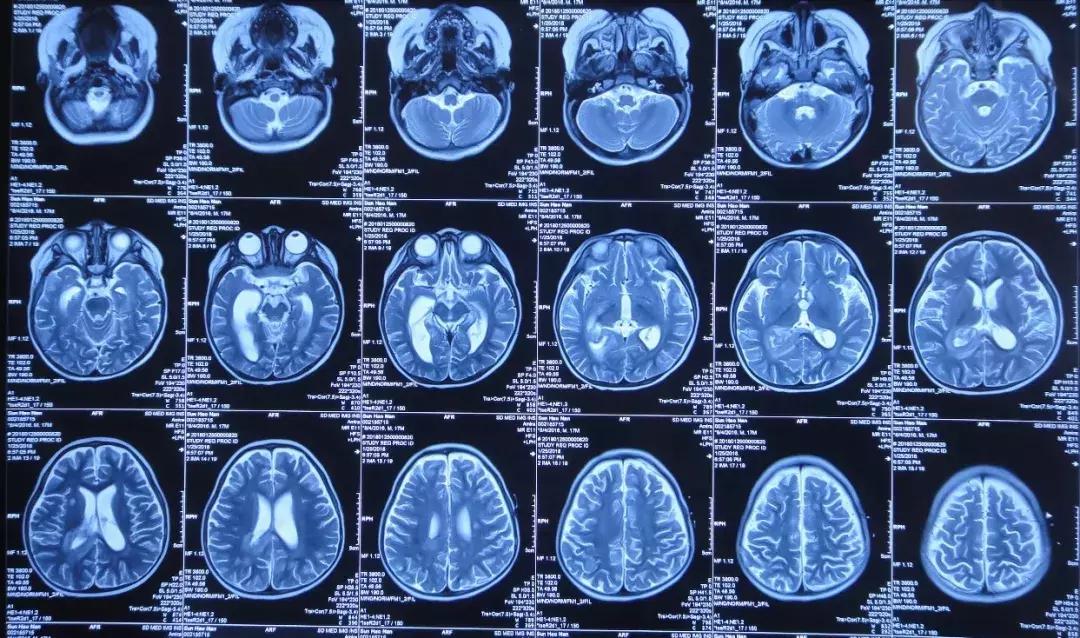

2018年2月7日头MRI:右侧积脓

2018年1月30日小浩浩入住北京某儿童医院,医生给予抗感染治疗,2月7日复查头MRI:右侧积脓,中线左移,大脑多发环状异常信号,2月9日接受了经右枕侧脑室腹壁外引流术(有分流泵),引流的脑脊液细菌培养未检出细菌,患儿术后仍有间断发热,期间加用人免疫球蛋白,2月26日加用两性霉素B抗真菌治疗,疗程7天,患儿期间仍有发热,精神差伴呕吐。